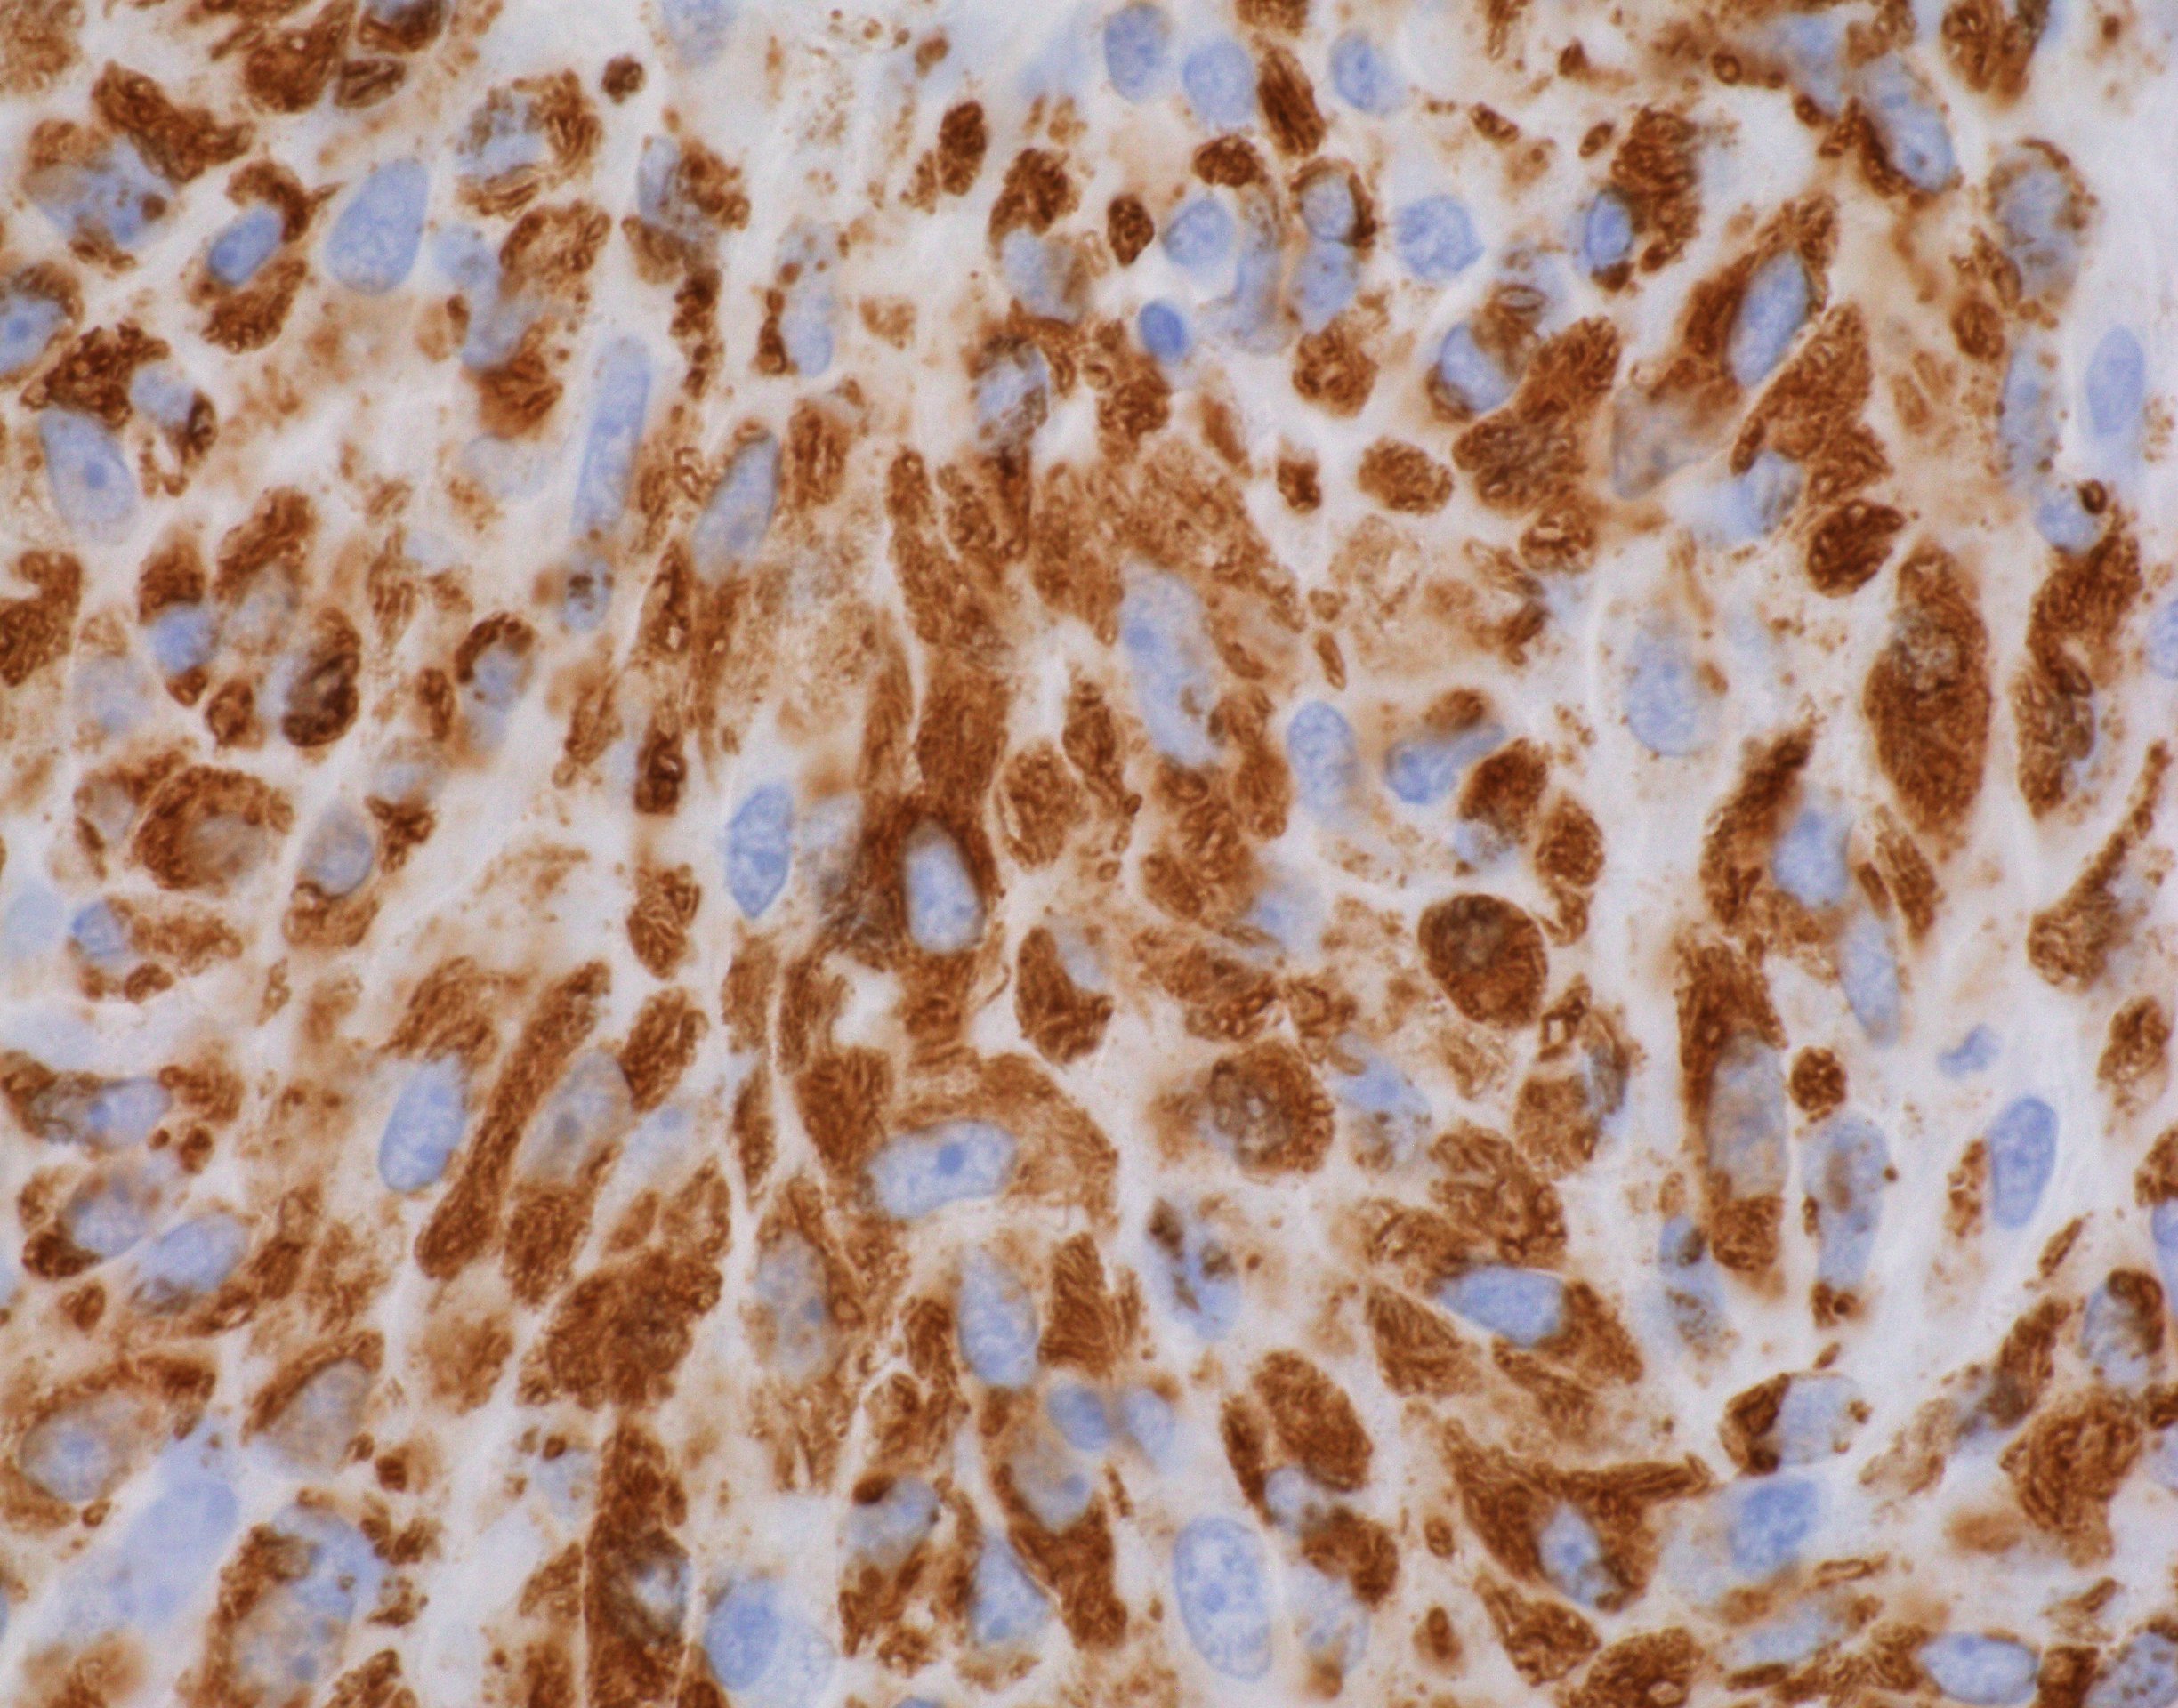

Microscopic (histologic) description

- Nodes show partial / complete effacement by storiform pattern of bland spindle cells, some with vacuoles

- Numerous vessels lined by plump endothelial cells, plasma cells and lymphocytes

- No multinucleated tumor cells, no foamy histiocytes

Microscopic (histologic) images

Contributed by AFIP and Chunyu Cai, M.D., Ph.D. (Case #532)

Positive stains

- Kaposi sarcoma:

- Fascicular spindle cells, slit-like spaces, mitotic figures, no granular or acidophilic cytoplasm

- Spindle cells are CD31+ and CD34+

- S100- and CD68- (Am J Surg Pathol 1999;23:656)